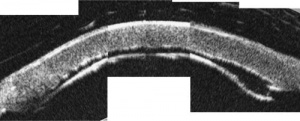

DALK techniques can be divided into two main categories. In "pre-Descemet membrane" procedures, some stromal layers remain adherent to DM. "Descemet's membrane" procedures involve complete stromal dissection and baring of DM. In all the techniques, a partial-thickness trephination of the cornea is performed depending on pachymetry.

The “big-bubble technique” was developed by Anwar and Teichman by utilizing the naturally occurring virtual space between the posterior stroma and DM[25]. A 300 to 400 um deep trephination is performed first. Next, a 27 or 30 gauge needle, bent to 30 to 40° 5 mm from its tip is advanced with the bevel facing down through the trephination groove and into the paracentral corneal stroma parallel to DM. Air is then injected forcibly either through the needle or through a dedicated DALK cannula, such as a Sarnicola or Fogla cannula. Air will move through the central cornea and extend radially cleaving a plane between the pre-Descemet's layer and the overlying stroma, forming what is called a Type 1 Bubble. Alternatively, the air injection may first extend peripherally and then expand centripetally, cleaving a plane between the DM and the pre-Descemet's layer, called a Type 2 bubble. A mixture of these two bubbles may also occur. Viscoelastic or saline solution can also be used for this step, though fluid injections diffuse through the stroma less easily and carry a higher risk of perforation. The epithelium and anterior stroma can then be removed. A sharp 30° blade is then used to puncture the anterior (posterior stromal) wall of the bubble, and blunt scissors can be used to cut the stroma into quadrants and excise it within the trephination. Once the pre-Descemet's layer or Descemet's membrane is bared, the donor button can be sutured in place.